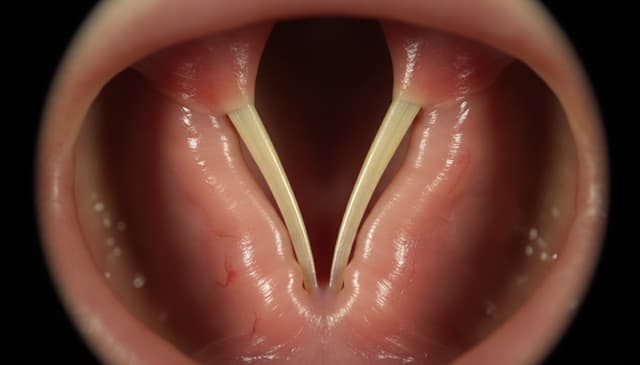

Czy septoplastyka to konieczność czy moda? 7 szokujących faktów

Septoplastyka w 2026 – poznaj fakty, mity i ukryte koszty. Zaskakująco szczery przewodnik po operacji przegrody nosowej. Sprawdź, zanim zdecydujesz!